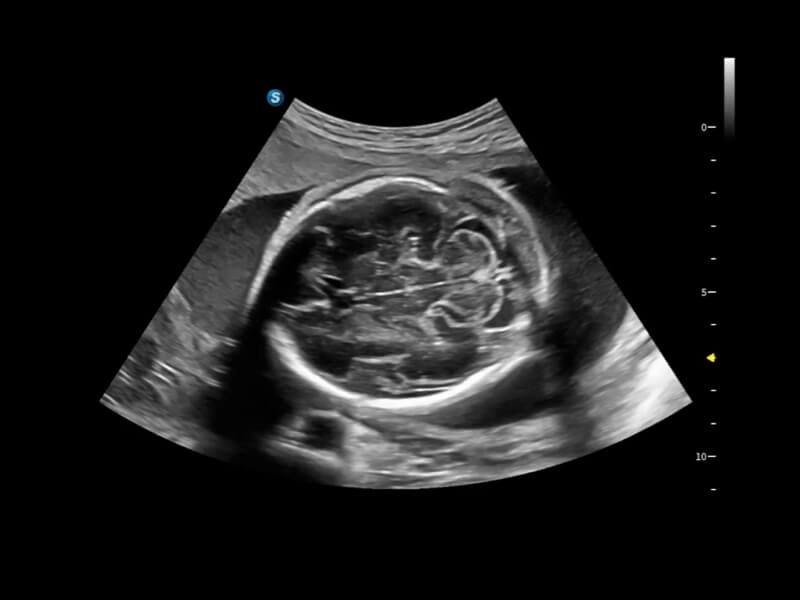

• One-Stop-Lösung zur automatischen Standard-Flugzeugerfassung und -messung. Mit nur einem Klick werden 29 Standardabschnitte von fetalen Ultraschallbildern intelligent identifiziert, und 13 biometrische Messungen werden automatisch mit hoher Intelligenz, Genauigkeit und Effizienz erfasst, um eine beispiellose Leichtigkeit während des Betriebs zu ermöglichen.